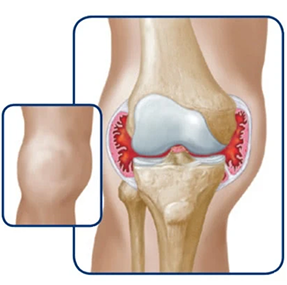

Joint bleeds—also called hemarthrosis—can happen when a joint is stressed. Repeated bleeds in the same joint may lead to chronic synovitis, where the joint lining becomes swollen and thick. Over time, this can limit movement and cause lasting joint damage.

The bleed starts to enter the joint

The joint swells

If bleeds continue, it can degrade the cartilage and bone within the joint.

Over time, the joint may swell, change shape, and lose mobility.